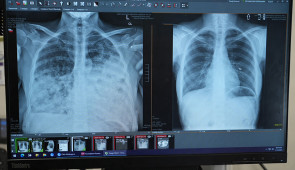

Lung cancer patient scans before and after transplant.

Dr. Ankit Bharat looks at chest scans.